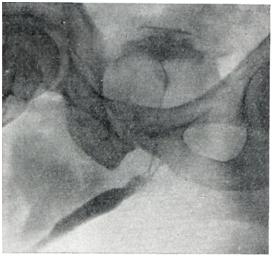

Применяют экскреторную урографию, цистографию и уретроцистографию; наиболее рациональна лакунарная уретроцистограмма по Кнайзе и Шоберу (рис. 4). Кислород, введенный по катетеру в количестве 150—200 мл, растягивает мочевой пузырь в виде купола. Введенное вслед за кислородом жидкое контрастное вещество (20% раствор сергозина в количестве 20 мл) располагается в области дна мочевого пузыря, выявляя внутрипузырный рост аденомы предстательной железы. Этим методом определяют ряд типичных рентгенологических симптомов: «берета» (рис. 5), удлинения мочеиспускательного канала (рис. 6), «клинка сабли» (рис. 7), приподнятого дна.